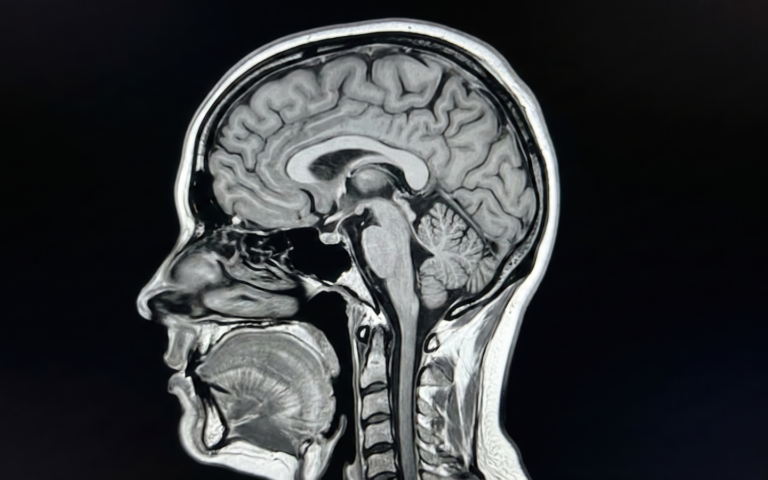

A diagnosis of a neurological disorder often comes with a heavy emotional weight. Patients are…

Neurological disorders can change life in an instant—or gradually over years. Whether it is Parkinson’s…